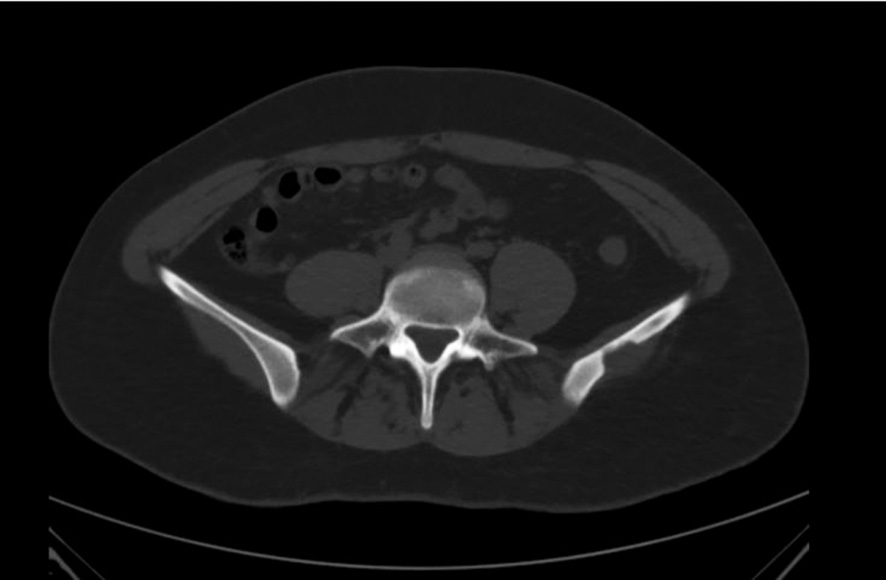

The studies of the pelvis were performed using magnetic resonance imaging (MRI) and computed tomography (CT). MRI revealed a cystic formation measuring 2.2 × 1.4 × 2.0 cm on the gluteal surface of the upper sections of the left iliac crest, along with edema of the musculus gluteus medius with a vertical length of up to 7 cm. A trabecular edema of the iliac crest on the left with a length of 5.0 cm was determined. The CT scan showed an osteolytic focus of the upper sections of the wing of the left iliac bone of up to 1.8 × 1.2 × 1.2 cm with clear uneven contours, destructed cortical layer of the bone, and signs of generalization beyond its limits (Fig. 1).

Fig. 1. Computed tomography reveals an osteolytic focus in the wing of the left iliac bone.